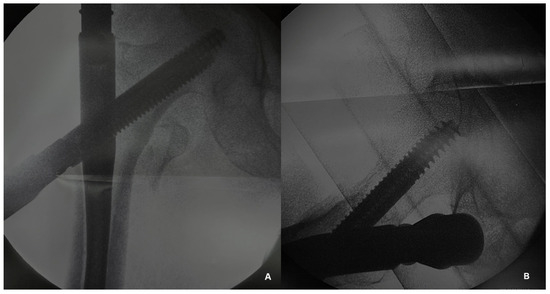

All the patients were treated with intramedullary nail fixation (Figure 1) by the same surgical team. The operation was performed 24–48 h after the injury.

Figure 1.

Intraoperative radiographic assessment during the intramedullary nailing of an intertrochanteric fracture. (A) Anteroposterior view and (B) lateral view.